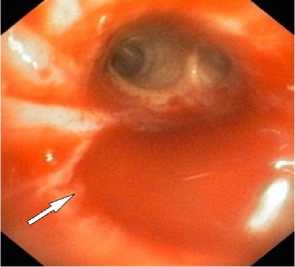

Рисунок 8. Ангиограмма правой внутренней грудной артерии (ПВГА) у пациента с ЛК 2А, клапанная эндоблокация): а – гиперваскуляризация нижней доли правого легкого; б – состояние после эмболизации ПВГА микроэмболами (710–1000 мкм ) – заполнение только ствола ПВГА

Figure 8. Angiogram of the right internal thoracic artery (RITA) in a patient with PH grade 2A (valve endobronchial occlusion): a – hypervascularization of the lower lobe of the right lung; б – status post embolization of the RITA with microembolic particles (710–1000 μm) – filling of the RITA trunk only

Предполагаемые источники кровотечения эм-болизированы с помощью микросфер, желатиновых губок и спиралей (рис. 8, а, б). Комбинированное применение эндобронхиальной тампонады с эмболизацией бронхиальных артерий выполнено у 13 (8,7%) пациентов и позволило во всех случаях добиться прекращения поступления крови в трахеобронхиальное дерево и избежать асфиксии (рис. 8, в, г).

Рецидив ЛК после эмболизации наблюдался у 15 (10%) пациентов, в 3 случаях из них эмболизация БА была выполнена более года назад. В результате ангиографического поиска выявлены дополнительные источники ЛК: межреберные артерии – 4, внутренняя грудная артерия – 8 (рис. 8), АV – 3 (рис. 7).